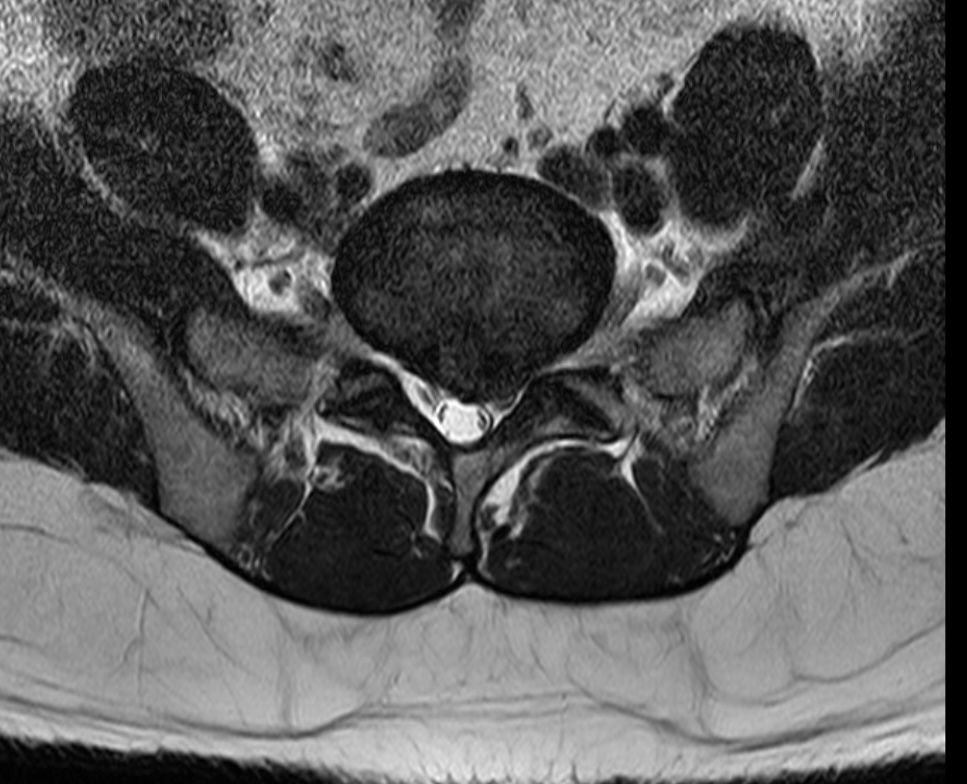

2. 아래 첨부한 사진이 제 MRI 사진인데 집에서 요가매트로 간단하게 할만한 스트레칭 자세 추천해주실수있을까요?

• 1번 째 사진

• 2번 째 사진